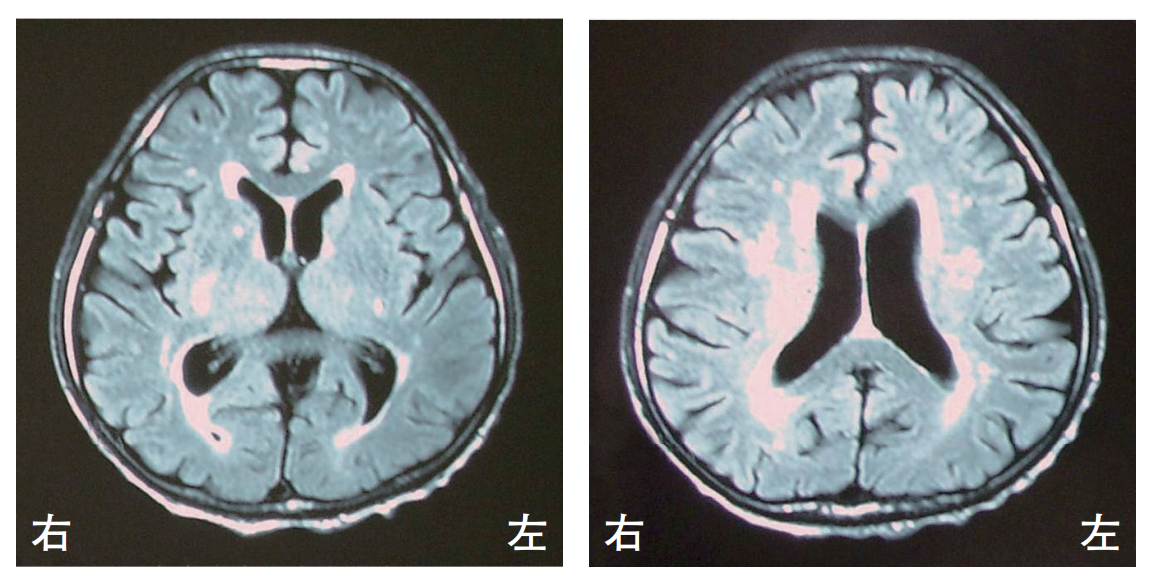

82歳の女性。高血圧と糖尿病の治療を長期にわたり行っている。徐々に歩行障害がみられるようになり、転倒することが多くなった。頭部MRIのFLAIR像を別に示す。

画像所見で考えられるのはどれか。